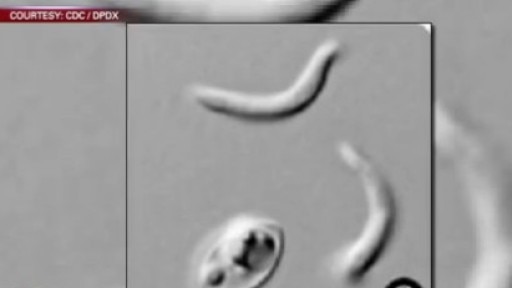

Cause Unknown for Cyclosporiasis Outbreak

First reports of the Cyclosporiasis outbreak started coming into the state health department back in May.?